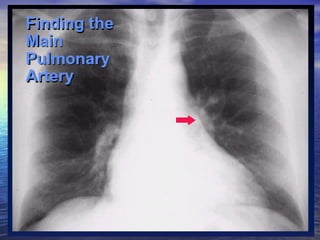

Main pulmonary artery big Normal Vasculature               Pulmonic stenosis                                      Idiopathic pulmonary artery dilatation               Hyperdynamic states  Increased flow (Left to right shunts)  ASD             VSD                                                           PDA                                                          Anomalous pulmonary venous return

Main pulmonary big (continued) Pulmonary venous hypertension                Presupposes left atrial enlargement  Pulmonary arterial hypertension  Lungs - normal             multiple pulmonary emboli, COPD ,  Lungs - abnormal Schistosomiasis

Main Pulmonary Artery concave Normal aorta  Cardiomyopathy  Normal vasculature                         Aorta prominent   Hypertension                      Aortic regurgitation        Ascending aorta prominent  Aortic stenosis